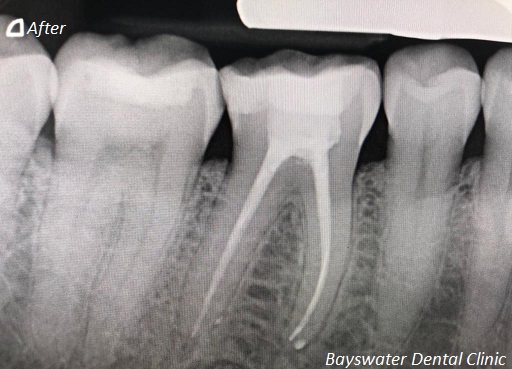

Root Canal treatment on Lower molar tooth immediate after the Root Filling!

before

after

Root canal treatment on three rooted tooth! which had 4 canals!